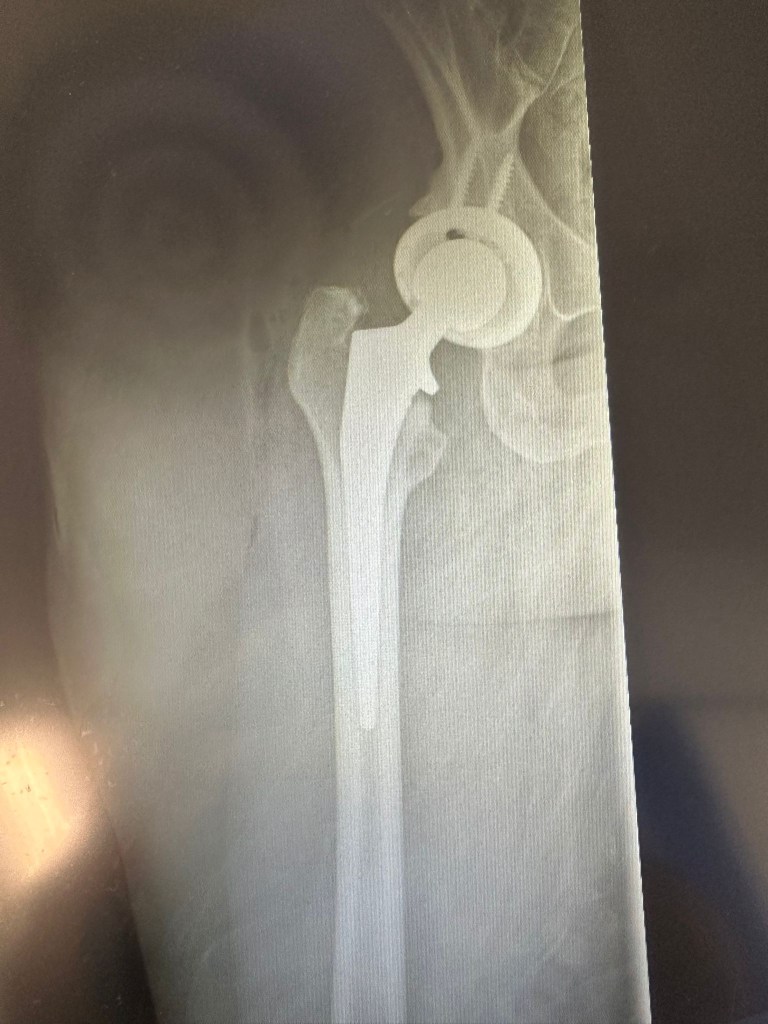

In other news, I have a new hip and am still signed off work. I’m 8 weeks post op today and it feels both slow and like I’ve been off for ages at the same time. Apparently lots of people go back to work around the 8 week mark but my query was met with a firm ‘not for teachers’ so I’ve got a few more weeks to go. I should probably be able to write a whole book but I’m surprised at how fuzzy my brain feels and how tired I get even walking to the park. The cats are very happy to have someone permanently sitting around though the dogs are annoyed I can’t get on the floor to give them belly rubs.

I am now part machine!